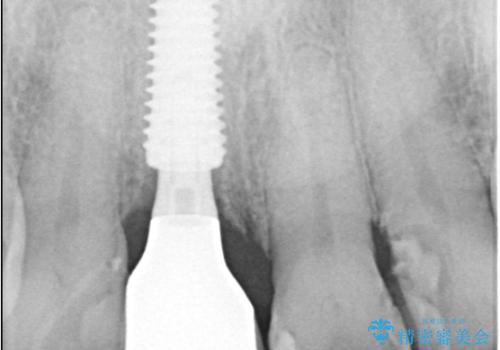

- 右上の前歯(1番)が折れたことを主訴に来院されました。診察とレントゲン検査の結果、歯冠の大部分が失われ、歯根の先には根尖病変(膿の袋)も認められました。残存歯質がほとんどなく、歯を保存することが困難と判断し、抜歯が必要と診断しました。

治療は、まず感染の原因となっていた前歯を慎重に抜歯し、抜歯と同時にインプラントを埋入しました。審美性を重視する部位であるため、骨や歯ぐきのボリュームを維持するための補填処置も併用しています。術後は仮歯を装着し、見た目を保ちながらインプラントと骨がしっかりと結合するのを待ちました。

約3か月の治癒期間を経て、最終的にセラミックの上部構造を装着。周囲の歯や歯ぐきとの調和を図りながら、自然な見た目としっかりとした噛み心地を再現しました。患者さんからは「折れて落ち込んでいたが、見た目も噛み心地も元通りで嬉しい」とのお声をいただきました。即時埋入により、精神的な負担も少なく治療を終えることができました。